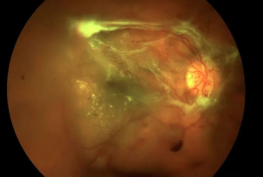

牵拉性视网膜脱离

多由糖尿病视网膜病变、眼内出血/炎症引起,疤痕组织收缩牵拉视网膜所致,糖友需高度警惕。

· 孔源性/牵拉性脱离:选择27G玻璃体切割术,切口仅0.4mm,无需缝合,清除牵拉、封闭裂孔、注入气体/硅油固定,稳定。